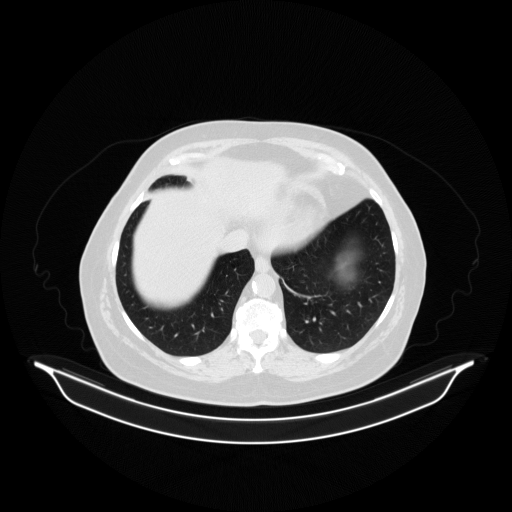

Generated VENOUS CT scan (A→B translation)

Full window (WL 1023.5, WW 4095 β†’ Low βˆ’1024, High +3071)

Actual HU range: [-1024.0, 1188.4]

Lung window (WL -600, WW 1500 β†’ Low βˆ’1350, High +150)

Actual HU range: [-1160.8, 150.0]

Mediastinum window (WL 40, WW 400 β†’ Low βˆ’160, High +240)

Actual HU range: [-160.0, 240.0]